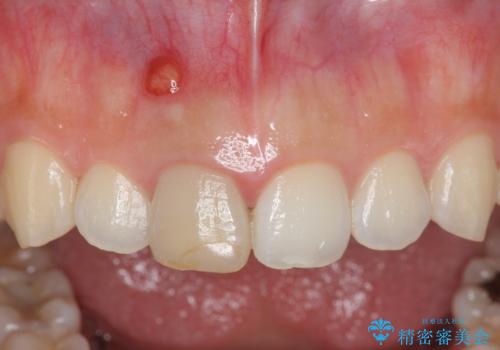

歯ぐきにできものができた 前歯の色調改善

- 歯ぐきに、にきびのようなものができ治らない、と治療を希望され来院されました。

根管治療を行ったことで、歯ぐきのできものは治癒し再発をしなくなりました。